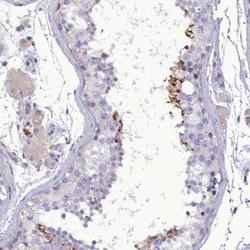

Supportive validation

- Submitted by

- Novus Biologicals (provider)

- Main image

- Experimental details

- Immunohistochemistry-Paraffin: FAM149B1 Antibody [NBP1-81452] - Staining of human testis shows strong cytoplasmic positivity in cells in seminiferous ducts.